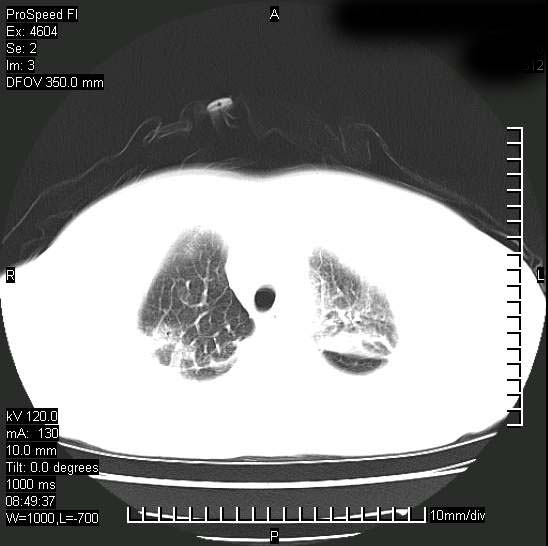

标题: CT15528:女性,79岁,近几日晚上高热,39度,仍咳少量血 [打印本页]

十几年前曾患肺结核,一周前突咳血约100ml,中性粒细胞稍高,诊断两上肺陈旧结核,下肺炎症,给予抗炎治疗,近几日晚上高热,39度,仍咳少量血,4天前ct及今天ct上传。

[face=黑体]8月30日[/face]

支持陈旧性肺结核并两下肺感染,两侧胸腔积液。

短短几天内,病变范围明显增多扩大,以左侧明显,而且双侧出现胸水,还是考虑感染.

支持  结核ban感染,节段性肺不张,支气管内膜结核可能

继发性结核感染加重。左侧合并有支气管内膜结核。

无论是肿瘤还是炎症4天的时间都发展够快的,并且还在治疗中,如果说是左肺癌那么右肺的病变不好解释,本人更加倾向于炎症,左肺舌叶支气管被痰栓或血凝块堵塞,造成阻塞性肺炎。

1)两肺结核并感染。2)不排除左肺上叶中央型肺癌并阻塞性肺炎、肺不张可能;建议行纤支镜检查。3)右肺门及纵隔淋巴结肿大。4)双侧胸腔积液。